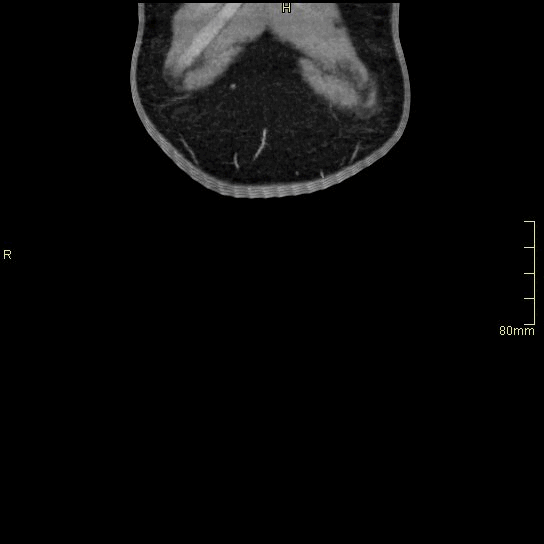

CT Abdomen Venogram - Soft tissue window (axial)